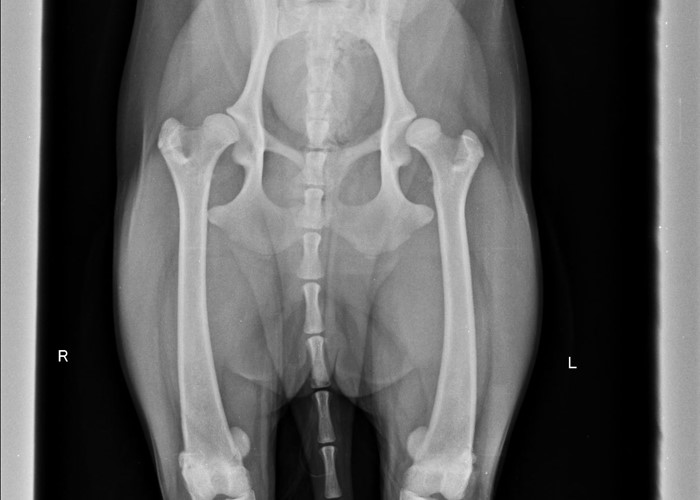

Les troubles orthopédiques sont fréquents chez le chien le chat mais aussi sur les très petits animaux comme le furet, le lapin ou les petits rongeurs.

Ils sont responsables de douleurs aiguës ou chroniques qui peuvent évoluer sans que l’animal ne se plaigne. Les affections orthopédiques peuvent être consécutives à un traumatisme comme une chute ou un accident de la voie publique, mais peuvent également survenir spontanément sans contexte traumatique en particulier chez les jeunes chiens encore en croissance et atteints de dysplasie de la hanche ou des coudes.

• chez les chiots en croissance pour dépister des pathologies de croissance ou congénitales